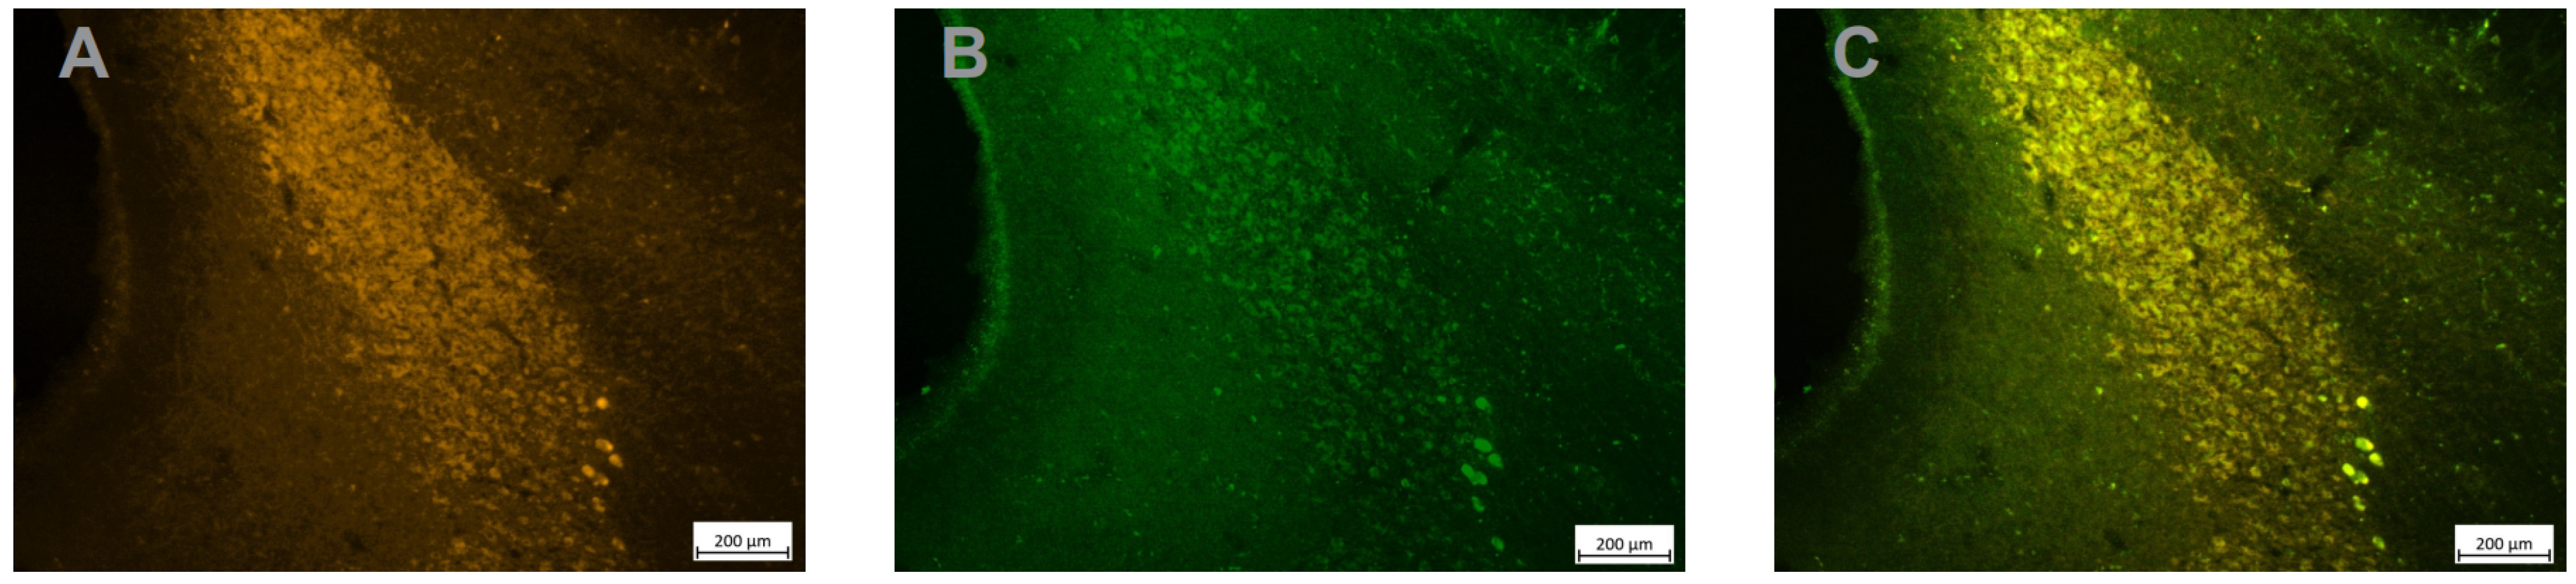

Figure 5. Strong DREADD expression in TH+ LC neurons. Adjacent sections treated with an anti-TH antibody (A), an anti GFP antibody to reveal the HM4Di-CFP DREADD (B) and an overlay of the 2 images (C) shows the perfect overlap between TH expression and DREADD expression in LC neurons.

Mounted sections were examined under a fluorescent microscope (Axioskop 2 plus, Leica). The first observations of TH immuno-labelled sections revealed a relatively high level of green fluorescence background (Figure 4A). Even if the signal was clearly stronger in the LC compared to the background, we decided to perform immunohistochemistry with diaminobenzidine (DAB) to confirm the specificity of DREADD expression in LC in another set of sections. Sections were pretreated with 20% methanol + 3%H2O2, 0.2% Triton X-100 and 10% normal goat serum + 10% Bovin Serum Albumin and then incubated in the antibody solution (IGg, anti-GFP, Abcam, ab 290, 1/750) for 24 h. This was followed by incubation in secondary biotinylated antibodies (1/125), then in avidin–biotin–peroxidase complex (ABC) solution, 0.01 M DAB (1/1) and 0.008% H2O2 for 10 min. Sections were mounted on gelatin slides and sequentially dehydrated in ethanol solutions (70, 80, 90, 100%) for 2 min. Then, the sections were incubated in xylene 3 times for 2 min each. As shown in Figure 4B, immuno-histochemistry confirmed the strong and specific expression of the HM4Di-CFP DREADD in the LC. Finally, as shown in Figure 5 the expression of the fusion protein hM4Di-CFP strongly overlapped with the expression of TH, which confirms that a majority of LC neurons expressed the hM4Di DREADD.